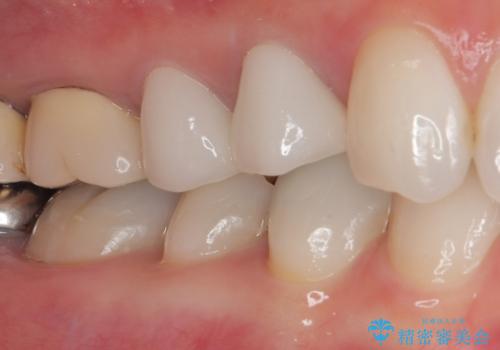

色がやや白いと感じましたが、ご自身でホームホワイトニングをされているそうで、今後周辺の歯を白くしていくとのことでした。

初回の根管治療で痛みや違和感は消退したため、その後は速やかに補綴治療を行いました。